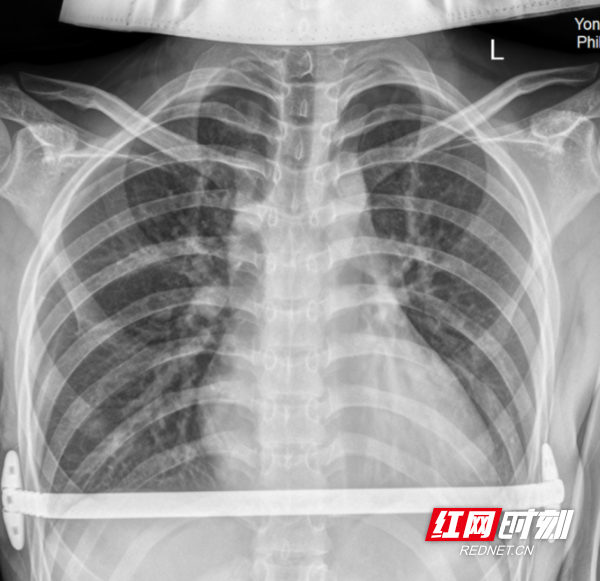

术后X片。

术后,医院发挥中西医协同康复特色,西医精准治疗+中医辨证调理、穴位按摩、膳食指导,加速伤口愈合、减轻术后不适。患者恢复迅速,无并发症,胸廓形态恢复正常,心肺压迫完全解除,重拾挺拔身姿与阳光心态。